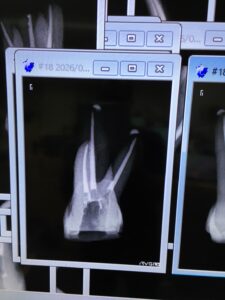

地方都市から来られているI先生のテストケースは以下だ。

日本では非難の?対象になるがアメリカだと絶賛されるシーラーパフの確認できる根管充填がなされている。

この事実一つとっても日本はもはや周回遅れと言ってもいいだろう。

そして一言、上手い!

下顎の近心根は術前にCBCTを撮影し、MB,MLが合流していると認識して合流の位置を確認して根管充填している。

これが

“わかっている人”

のなせる技だ。

全く問題がない。